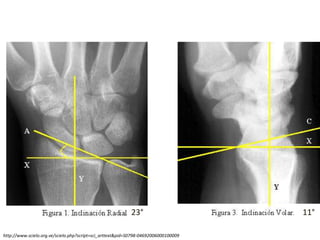

Imagen

AP , LATERAL Y OBLICUA

23° 11°

http://www.scielo.org.ve/scielo.php?script=sci_arttext&pid=S0798-04692006000100009

Goniometria

10mm 1-2mm

Diagnóstico: Radiológico

RX AP + LATERAL

AP

Acortamiento

radial

Inclinación radial 23

grados

Desplazamiento

Plano Sagital

Inclinación

Diagnóstico: Radiológico RX AP+ LATERAL AP Acortamiento radial Inclinación radial 23 grados Desplazamiento Radial Plano Sagital Inclinación Radial Desplazamiento TAC Fracturas intrarticulares Detectar hundimientos No congruencia Lesiones asociadas. RMN Lesiones ligamentares Fx Escafoides.